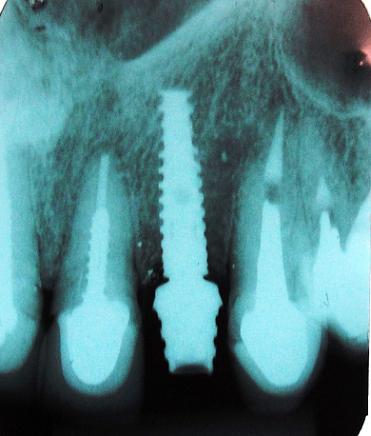

Radiografia do Implante Instalado com o provisório

Implante instalado e componente para prótese provisória